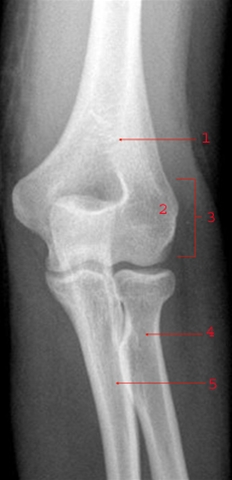

Bruddet sidder ved overgangen til spolebenshovedet i det område, der kaldes "collum" (halsen).

Brud i øvre del af spolebenet, ved overgangen til radiushovedet (som danner led med overarmsbenet), er en hyppig brudtype hos børn.

Diagnosen bekræftes ved røntgenbillede.